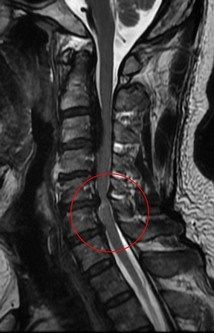

黃先生的頸椎第二節到第六節都有後縱韌帶骨化,其中第五、六節最為嚴重,脊髓已被壓得非常狹窄,核磁共振更可見明顯脊髓空洞,洪祥益主任說,這代表神經已受損,必須盡快手術,若再拖延,一旦跌倒、車禍或頸部突然甩動,都可能造成急性脊髓傷害,增加癱瘓風險。

左、中圖:黃先生的頸椎第二節到第六節都有後縱韌帶骨化,其中第五、六節最為嚴重,脊髓已被壓得非常狹窄,核磁共振更可見明顯脊髓空洞。